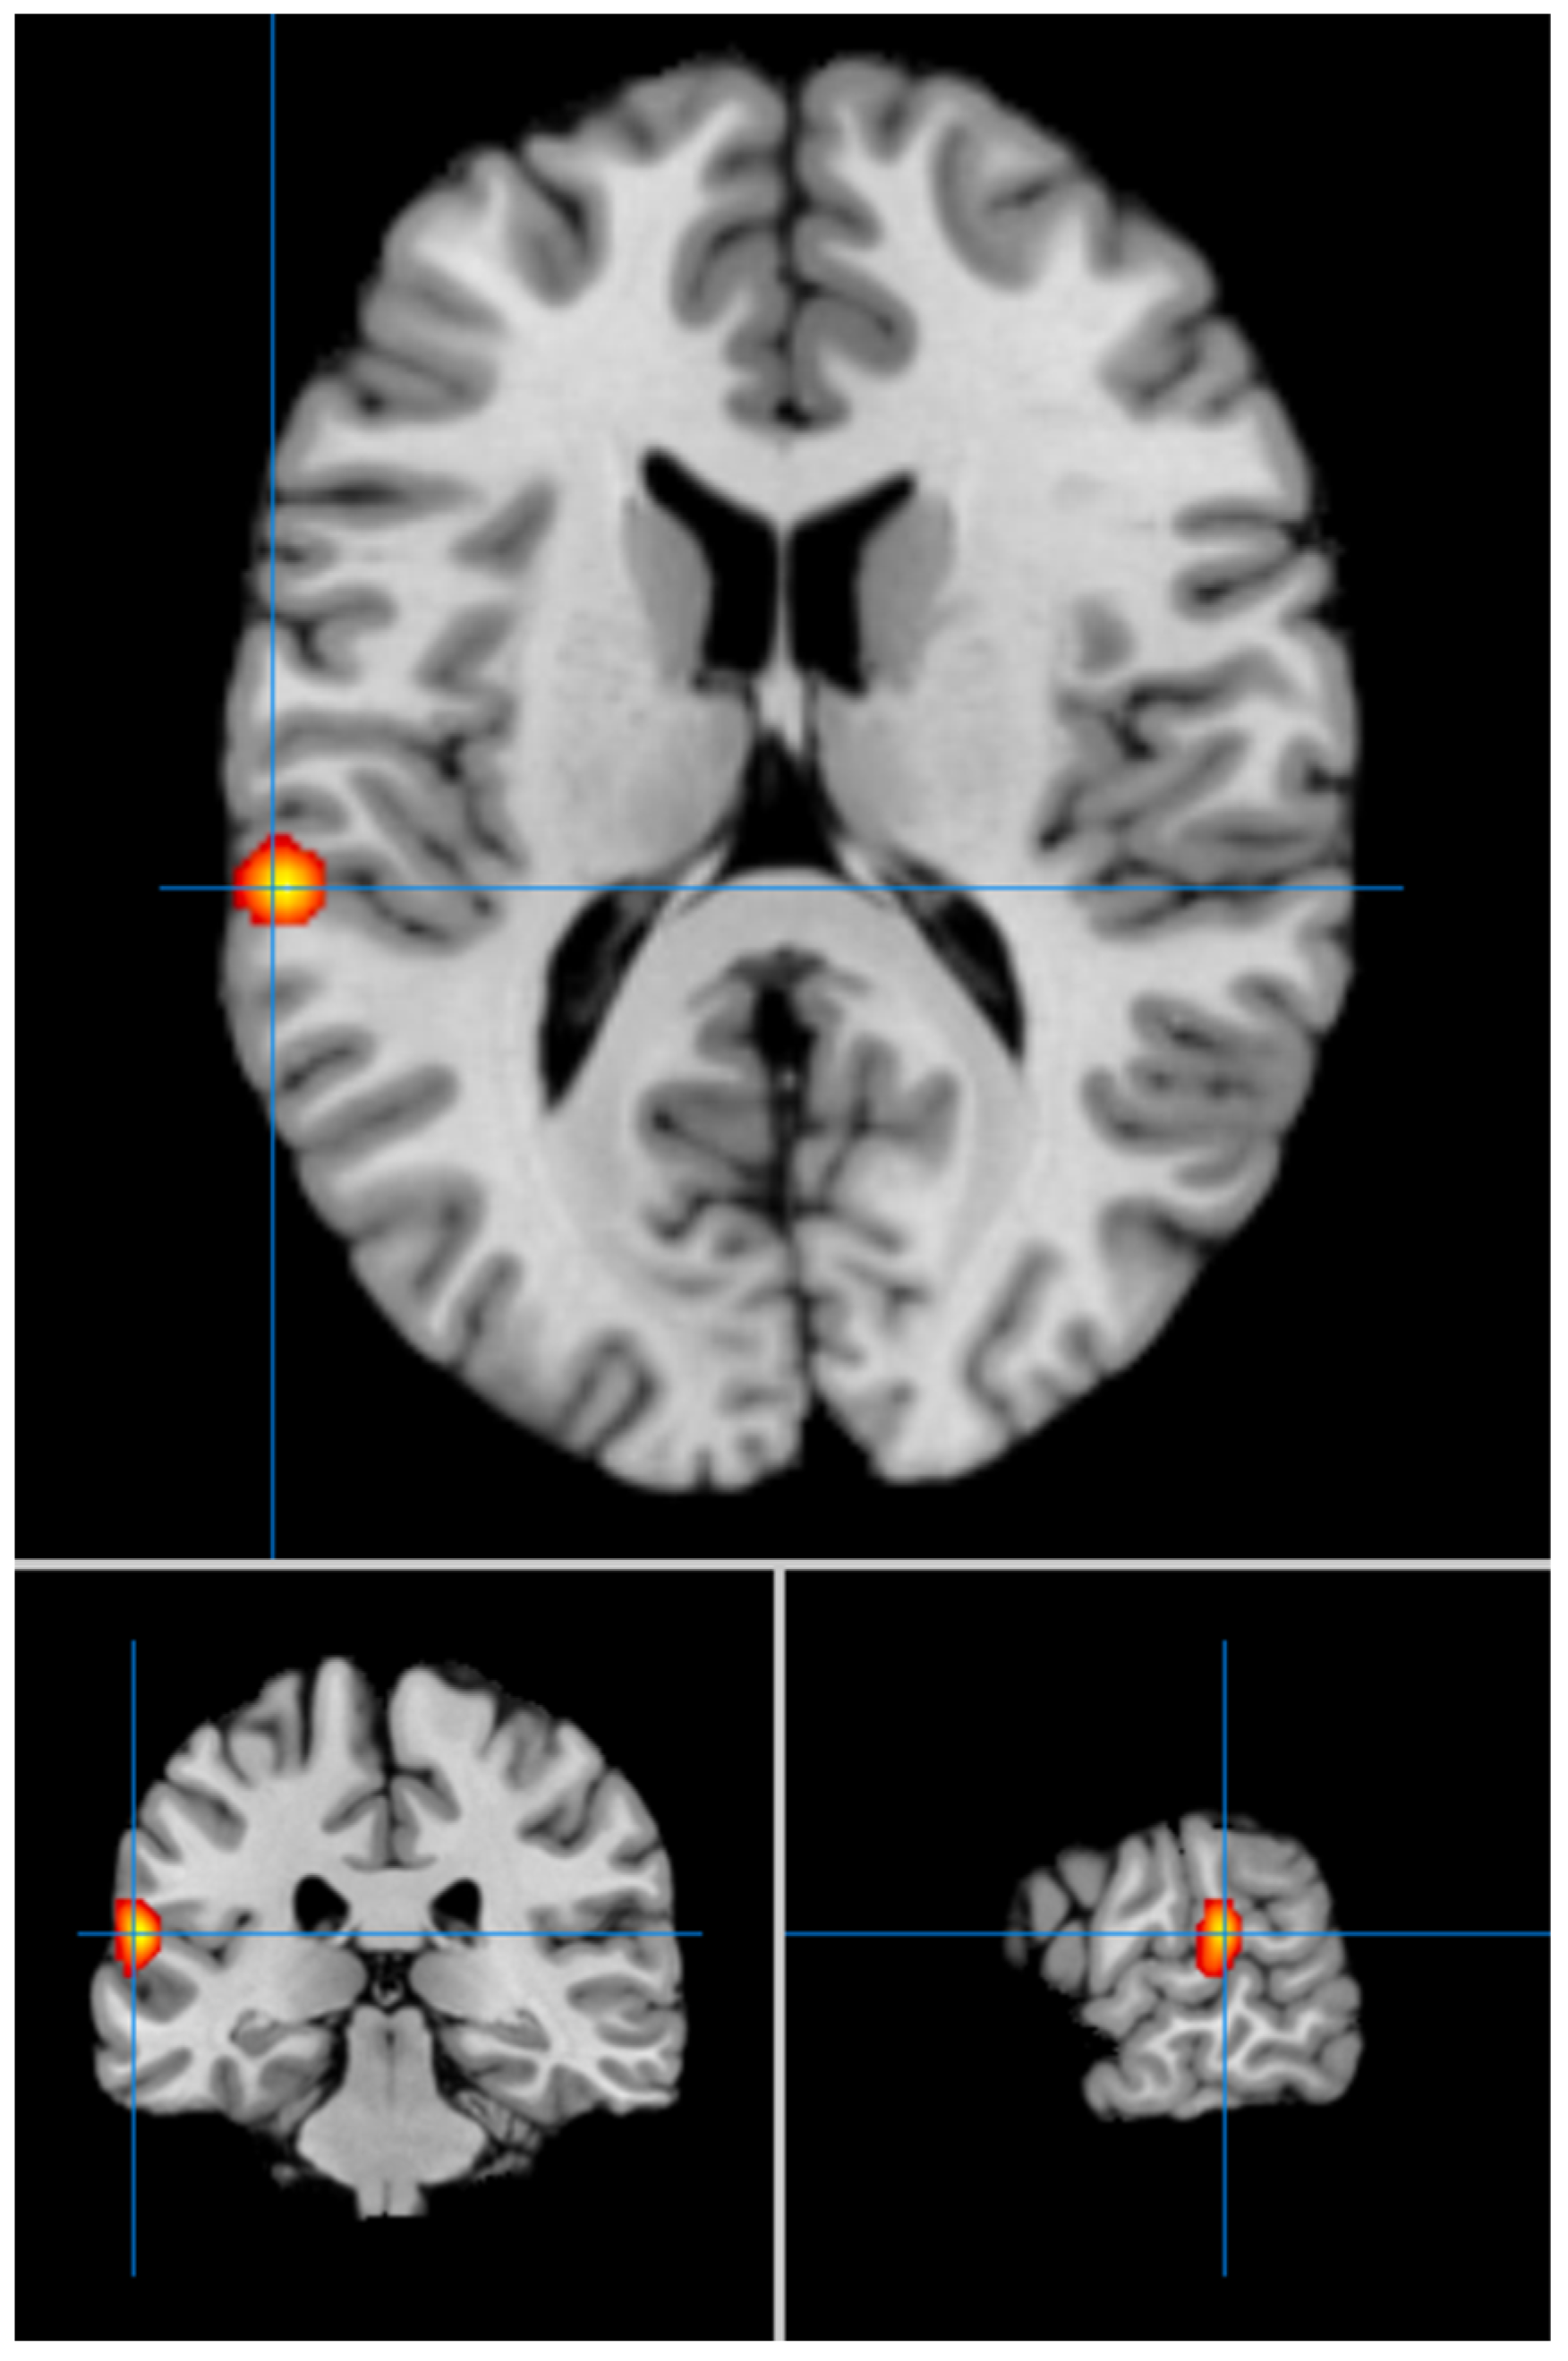

| 1 | −60 | −30 | 14 | 0.017 | 2.091 × 10−6 | 46.020.885 | Left STG, BA 42 ** |

| 2 | 18 | −50 | −8 | 0.014 | 4.14 × 10−5 | 39.361.618 | Right Cerebellum Culmen/Lingual gyrus * |

| 3 | 6 | 38 | 8 | 0.013 | 5.212 × 10−5 | 38.805.122 | Right ACC, BA 24 * |

| 4 | −48 | 20 | 16 | 0.013 | 6.311 × 10−5 | 38.337.176 | Left Inferior Frontal Gyrus, BA 45 * |

| 5 | −38 | −84 | −22 | 0.012 | 9.346 × 10−5 | 37.360.582 | Left Cerebellum Declive/Lateral Occipital Cortex * |

| Contrast: LLD < HCs | |||||||

| Cluster # | x | y | z | ALE | P | Z | Label (Nearest Gray Matter within 5 mm) |

| 1 | 4 | 32 | 44 | 0.017 | 2.175 × 10−6 | 45.939.293 | Right Medial Frontal Gyrus, BA 8 ** |

| 2 | 14 | 46 | 12 | 0.015 | 9.261 × 10−6 | 4.282.004 | Right Medial Frontal Gyrus, BA 9 * |

| 3 | −20 | −10 | 48 | 0.013 | 2.789 × 10−5 | 4.029.988 | Left Cingulate Gyrus, BA 24 * |

| 4 | −20 | 6 | 14 | 0.012 | 8.703 × 10−5 | 37.539.575 | Left Putamen * |

| 5 | −18 | 4 | 16 | 0.012 | 8.883 × 10−5 | 3.748.818 | Left Caudate Body * |